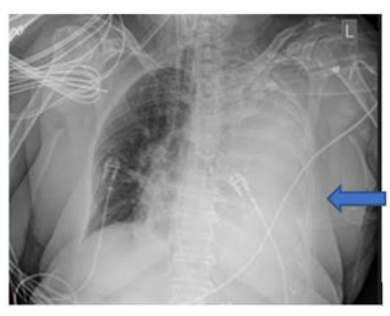

A 74-year.old woman with a past medical history significant for essential hypertension, former smoker, and goiter presented to the urgency room with dyspnea on exertion of one month of evolution, 'Ihe patient has no known asbestos exposure. Physical examination was remarkable for decreased breath sounds on the left hemithorax, Chest Xray was initially evaluated and showed evidence of near complete opacification of the left lung, Given this finding, a chest CT scan was performed which revealed a 15.1 cm x II cm x 19.3 cm extrapulmonary and intrapulmonary mass in the left hemithorax with compression and subtotal collapse of the left lower lung, A PET CT scan was also performed and showed a 13 cm FDG avid mass in the left chest involving nearly all the left lower lung, and the posterior segment of the left upper lung. This is a tool which helps to categorizæ the tumor between malignant and benign, depending on the of its metabolic activity

A CT guided core biopsy of the lesion was done, and pathology was consistent with a solitary pleural fibrous tumor. Immunohistxhemistry was strongly positive for CD34, STAT6, and negative for pankeratin. The patient was then referred to a thoracic surgery specialist for evaluation. She was taken to the operating room and underwent a tumor embolization, to reduce blood loss and then a complete tumor resection was perfromed. The surgery was successful with an encouraging prognosis.

In patients with a solitary fibrous tumor of the pleu- ra, a complete surgical resection with negative margin remains the treatment of choice in all cases, as performed in our patient. At this moment is controversial the role for conventional Che. motherapy or radiotherapy as adjuvant therapy in these cases. Vascular adhesions to adjacent visceral or parietal pleura are fre- quent leading to bleeding, however, formal lobectomy is rarely required. Benign SFTP has a high cure rate, Around 8% of pa. tients develop local recurrence, which is usually amenable to cu. rative re-excision, with an overall long-term cure rate of 88% to 92%, Patient tolerated the procedure and remained stable with. out recurrence,